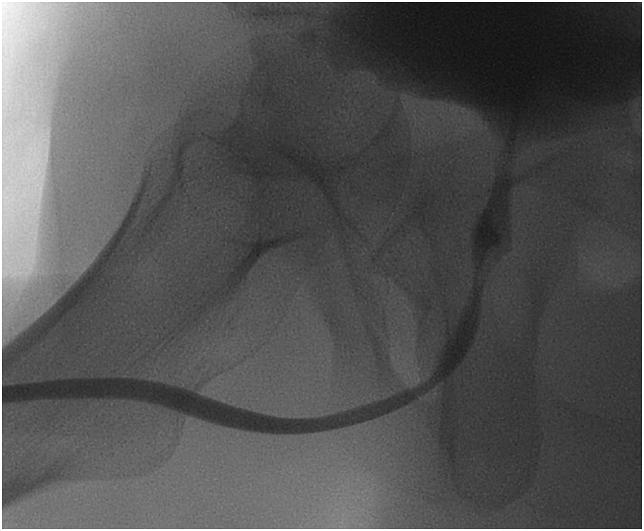

A failed end-to-end anastomosis after membranous urethral distraction injury post-trauma is a surgical challenge. We present a case of a young man after complex pelvic injury. Revision urethroplasty was done utilizing nerve and vessel sparing techniques. Intrasphincteric dissection enabled bulbous urethral pull-through with intrapelvic anastomosis with good success. Low dose tadalafil was given to optimize penile rehabilitation.

创伤后膜性尿道牵张损伤后端端吻合失败是一项外科挑战。我们报告一例复杂骨盆损伤后的年轻男性病例。采用保留神经和血管技术进行了尿道成形术翻修。括约肌内解剖实现了球部尿道经盆腔吻合后拖出,取得了良好效果。给予低剂量他达拉非以优化阴茎康复。